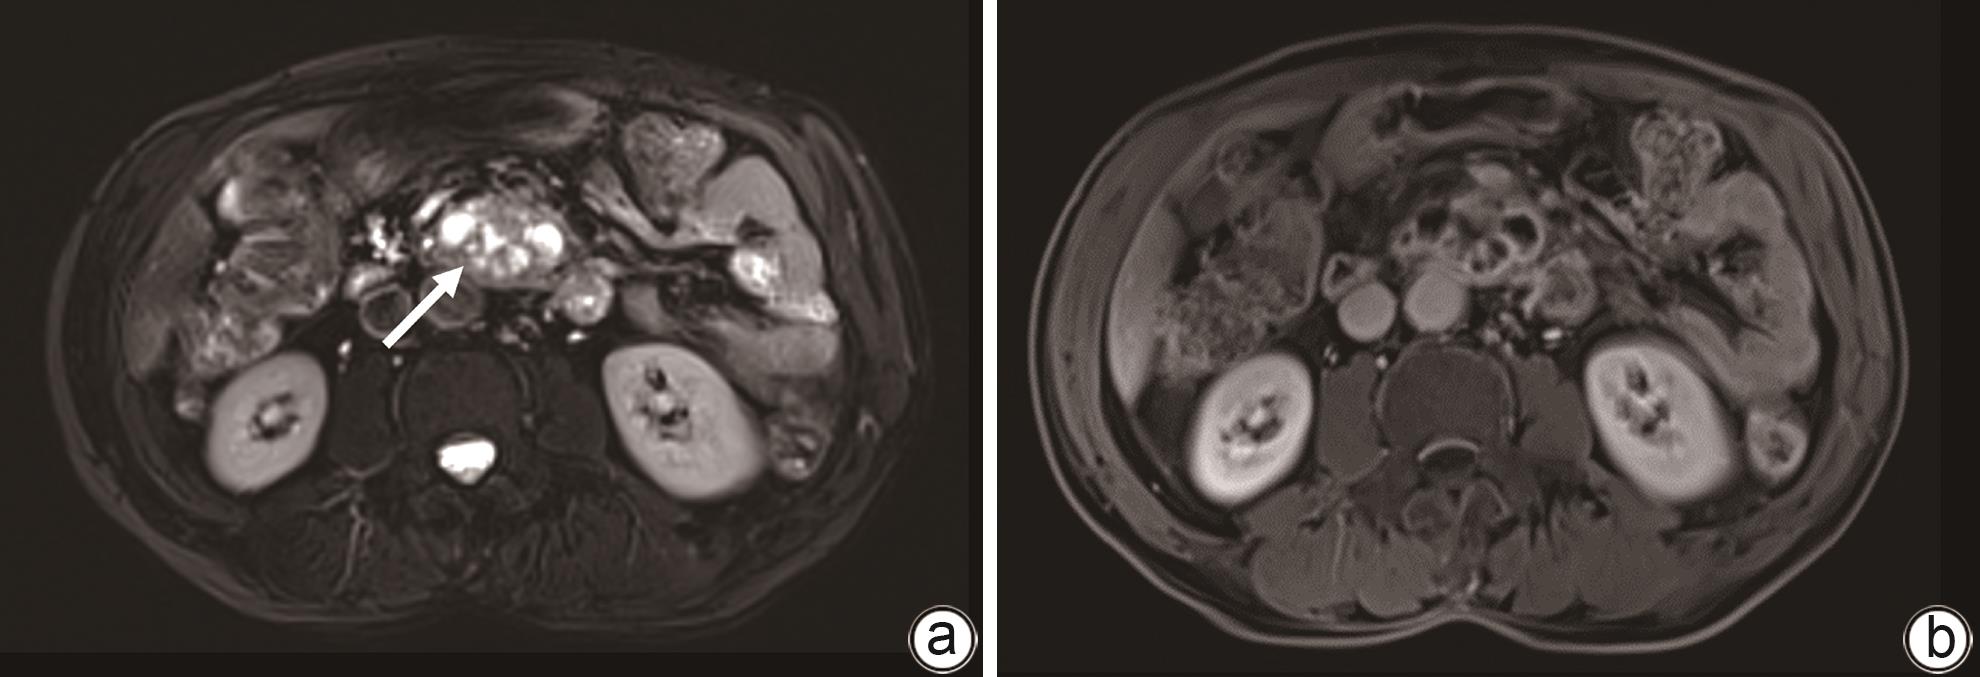

摘要: 目前,对于胰十二指肠切除术后胰瘘伴出血的治疗,血管介入和手术是主要的治疗手段,但以上治疗方法都存在一定的弊端,例如手术后出现再次胰瘘、出血、腹腔感染等并发症,介入治疗难以发现出血部位等。本文报道1例经引流管窦道置入Foley导尿管球囊压迫治疗胰十二指肠切除术后复杂性胰瘘伴静脉大出血患者。经导尿管球囊加压止血及有效引流,患者出血停止,消化道瘘痊愈,无胰腺假性囊肿、肠缺血、门静脉高压等并发症。Abstract: At present, vascular intervention and surgery are the main methods for the treatment of pancreatic fistula with bleeding after pancreaticoduodenectomy, but these treatment methods have certain drawbacks, such as the complications of pancreatic fistula, bleeding, and abdominal infection after surgical treatment, and interventional treatment sometimes fails to identify the bleeding site. This article reports a case of complex pancreatic fistula with massive venous hemorrhage after pancreaticoduodenectomy treated with Foley catheter balloon compression through the drainage tube sinus. Bleeding was arrested and gastrointestinal fistula was cured after catheter balloon compression and effective drainage, with no complications such as pancreatic pseudocyst, intestinal ischemia, and portal hypertension.